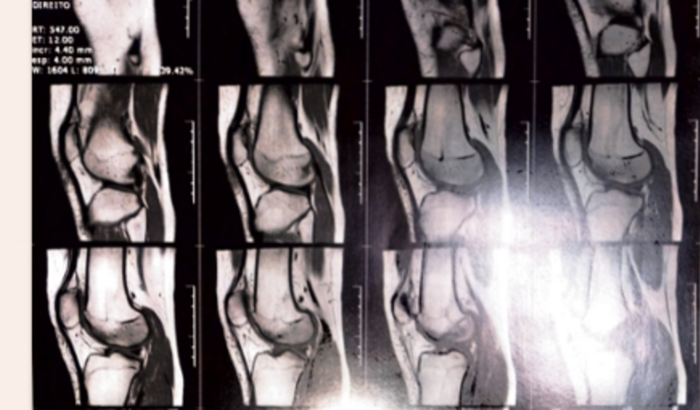

Eu sou Marianna atleta de vôlei amador do clube SOGIPA sou bolsista e esse ano vou precisar fazer cirurgia nos meus dois joelhos. Estou fazendo essa vaquinha porquê não tenho condições financeiras para pagar anestesia, fisioterapia, medicação e locomoção para o restante do tratamento. Desde já agradeço.